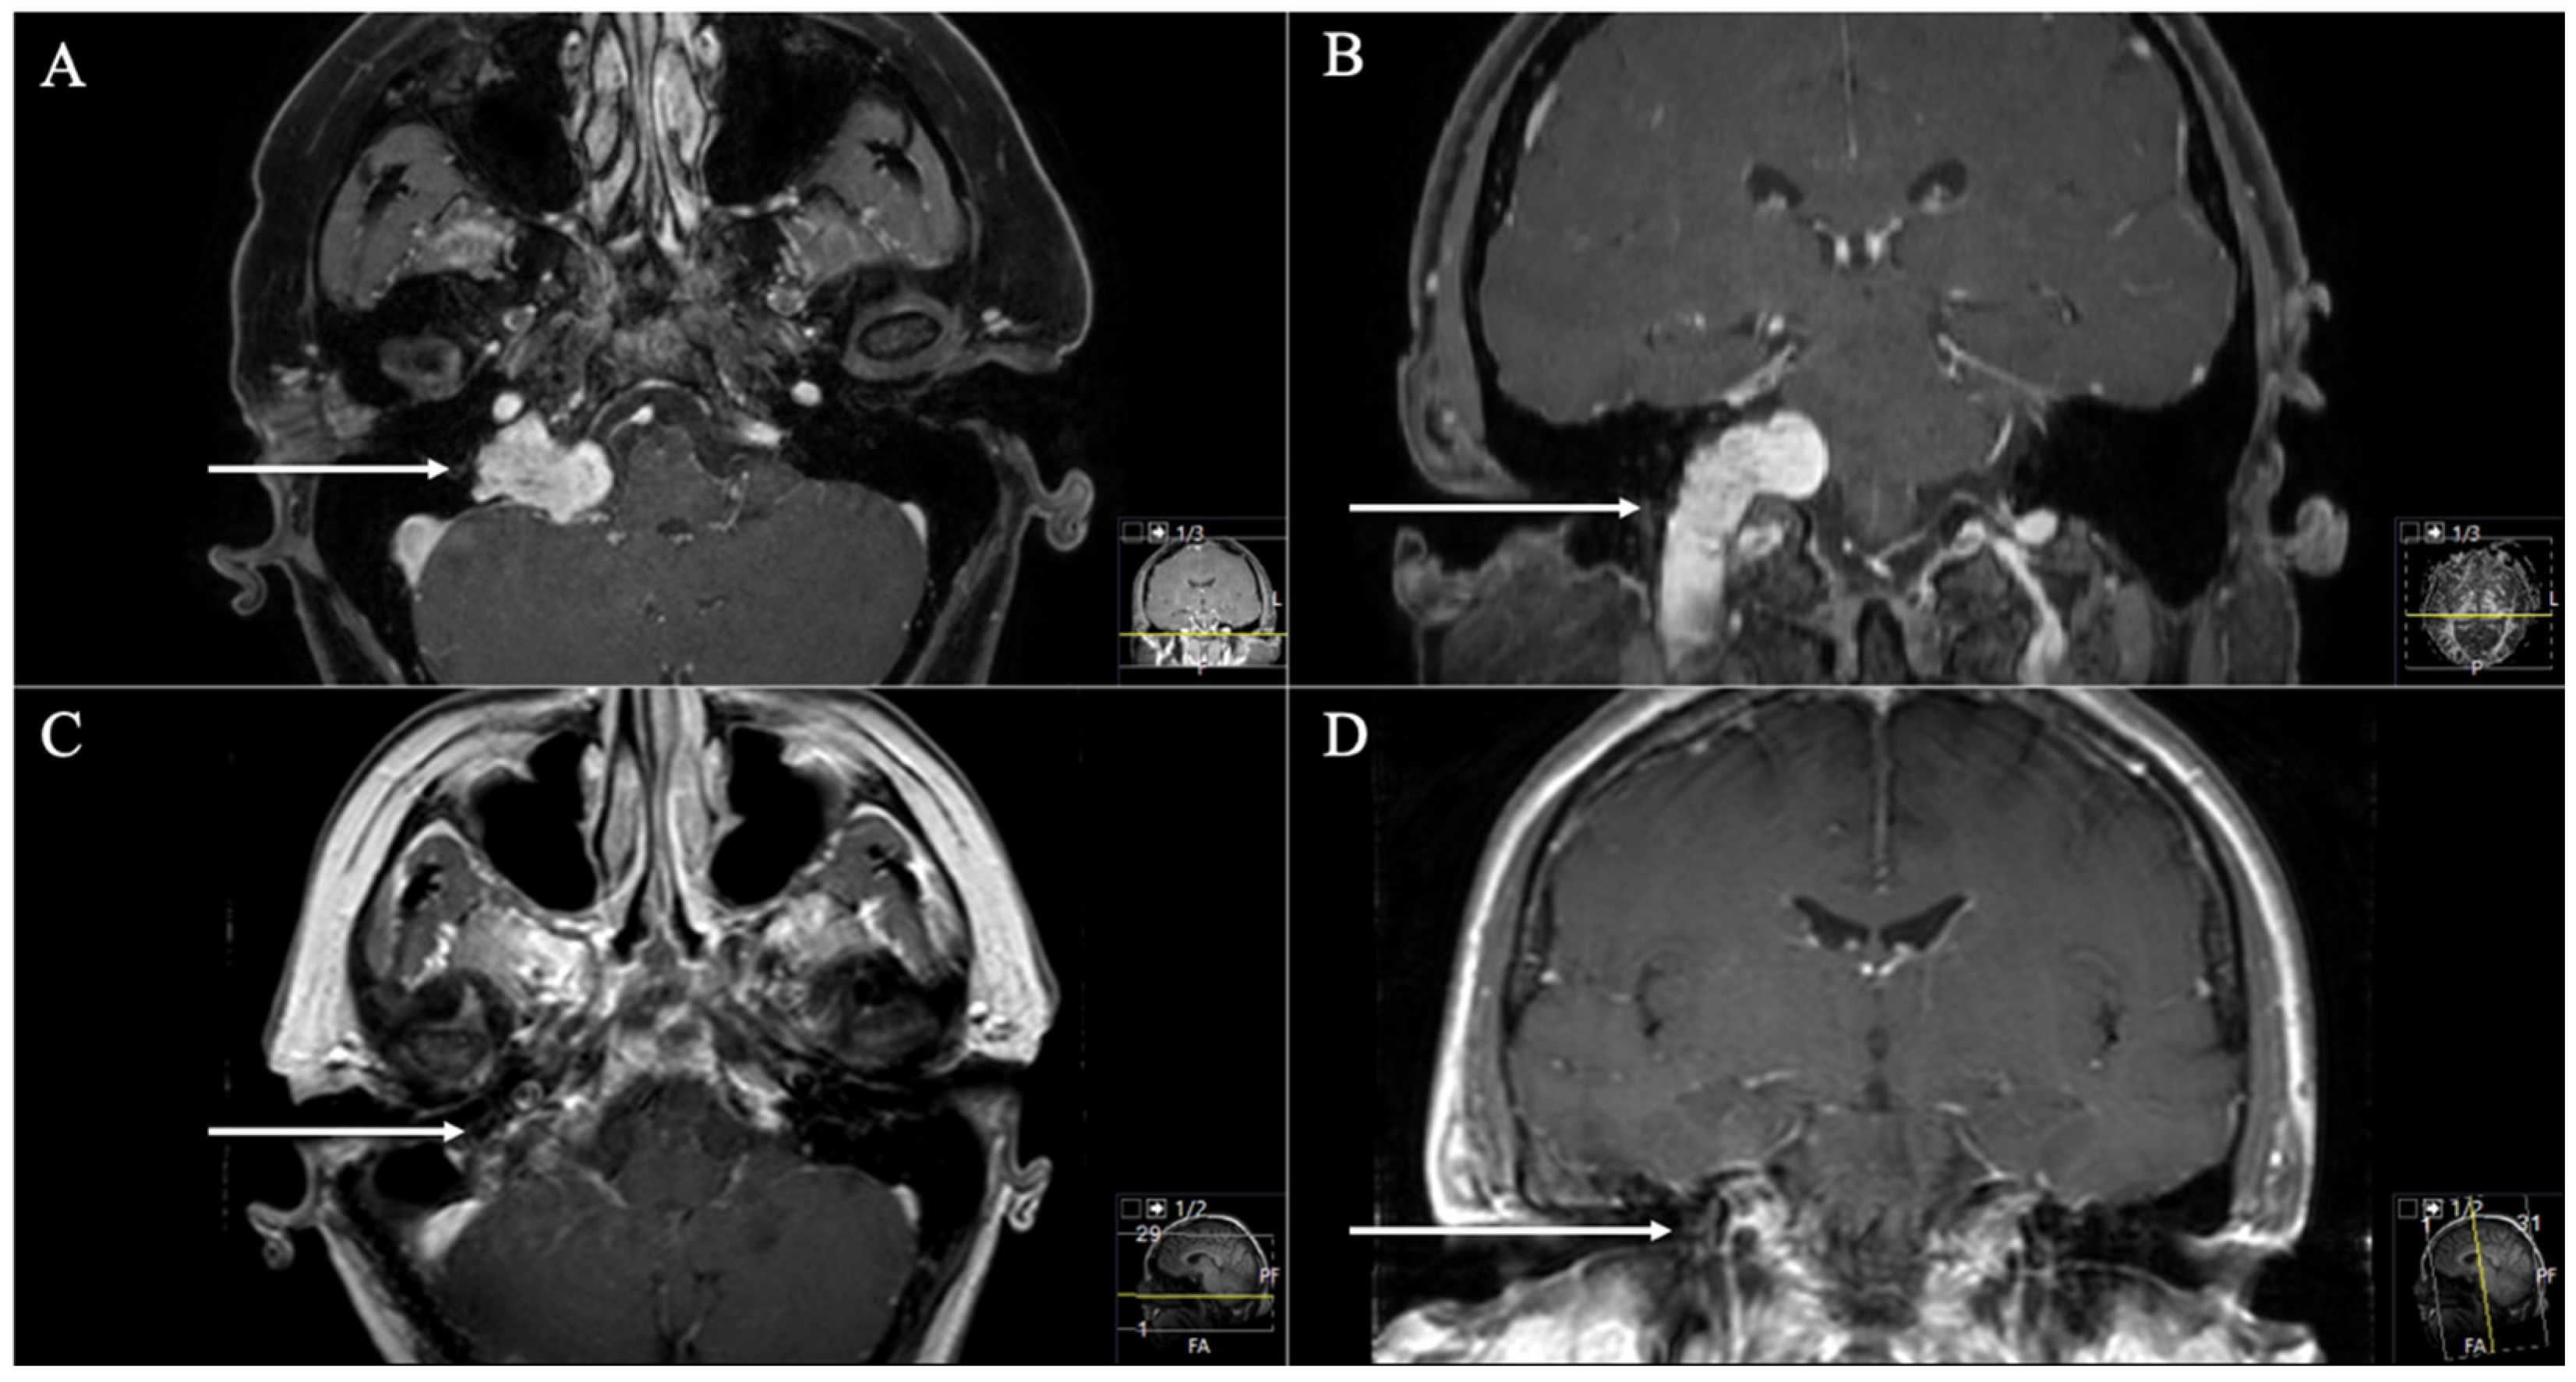

3. Results

3.1. Patient Population

3.2. Postoperative Outcome